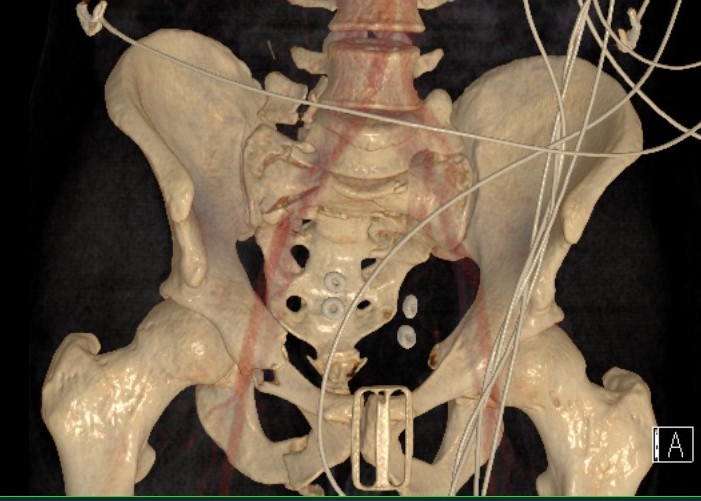

LC-1: pubic rami fracture with sacral fracture

Posterior fixation

Percutaneous sacroiliac screws

- external fixation

LC-1 with anterior external fixation Plating of bilateral pubic rami fractures